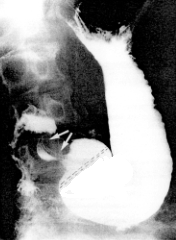

Landboe-Christensen (l944) studied the extent of the pyloric mucosal zone on the oral side by macroscopic tehcniques in 47 non-diseased, fresh post-mortem specimens. In all instances this zone was longer on the lesser than on the greater curvature, covering on average 7.2 cm of the lesser, and 5.2 cm of the greater curvature. The average percentage of the lesser curvature covered was 44 percent, and the average percentage of the greater curvature covered was 12 percent. The border between pyloric and oxyntic mucosa was irregular, often dentate or tortuous, and as a rule a number of islets of oxyntic mucosa were encountered in the pyloric zone. There was a transitional area of varying width between the two zones. In practice, a line drawn from the junction of the upper three- fifths and lower two-fifths of the lesser curvature, running downwards and to the right, indicates the approximate boundary of pyloric mucosa (Fig. 5.1).

![]() |

| Fig. 5.1. Relationship between pyloric sphincteric cylinder and pyloric mucosal zone in normal stomach. Arrows, contracted sphincteric cylinder; broken line, approximate border between pyloric and oxyntic mucosal zones. |

The mucosal folds in the pyloric region can be demonstrated readily in the intact, living human stomach by radiographic techniques. Swallowing a few mouthfulls of a suitable barium sulphate suspension on the empty stomach, and applying graduated compression on the anterior abdominal wall, shows the folds to advantage (Chap. 13). By means of image intensification and TV monitoring the movements of the mucosal folds may be studied (Chap. 13).

The position or direction of the mucosal folds during life depends mainly on the degree of contraction or relaxation of the muscularis externa. In his epic studies Forssell (l923, l934, l939) demonstrated "independent but co-ordinated" contractions of the muscularis externa and mucosa (brought about by contractions of the muscularis mucosae). One of the best examples of this phenomenon is seen during contraction of the pyloric sphincteric cylinder. Normally, when the cylinder is relaxed, its mucosal folds are circular; during contraction the folds change in direction, and with maximal contraction only longitudinal folds are seen in the fully contracted cylinder (Chap. 13).

Two anatomico-functional divisions of the pyloric part of the stomach are clearly identifiable. The first, the muscular pyloric sphincteric cylinder, is a tube of thickened muscularis externa, approximately 3.0 to 5.0 cm in length when fully contracted (in adults). It is definable in morbid anatomical specimens, in which it is seen to end in an aboral thickening, the pyloric sphincteric ring (which forms the peripheral part of the pyloric ring) (Chap. 3, 11). The pyloric sphincteric cylinder is also clearly definable in radiographic motility studies during life (Chap. 13).

Anatomically the pyloric mucosal zone differs from the sphincteric cylinder in extent as well as in shape. In the normal stomach the mucosal zone is longer than the cylinder, especially on the lesser curvature. While the cylinder is roughly triangular in shape or fan-shaped, with the apex on the lesser and the base on the greater curvature (when contracted), the greatest length of the mucosal zone occurs on the lesser curvature (Fig. 5.1).